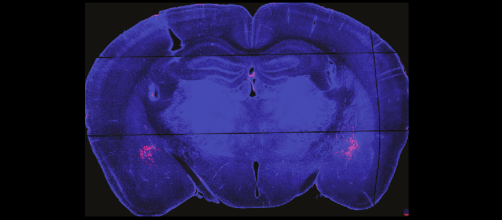

Des cellules programmées pour cibler les tumeurs cérébrales

Notre état d’attention dépend d’une poignée de neurones

Un cerveau trop ou pas assez synchronisé prédirait la psychose

Le double visage du fentanyl: les bases neuronales de l’addiction aux opiacés